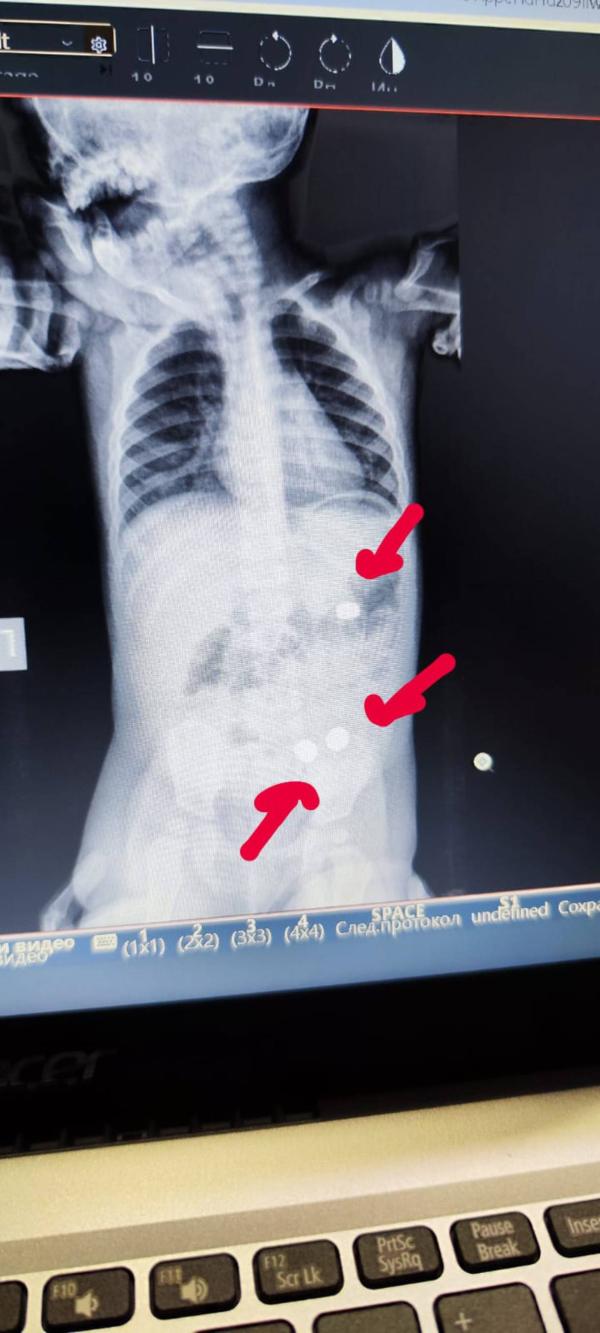

А что дальше...а дальше: страх, паника, больница, рентген, отказ от наркоза и ФГДС, ожидание в стрессе в течении суток, поиск батареек в каждом подгузнике и облегчение, когда все 3 батарейки благополучно вышли.

-по рентгену 2 батарейки уже были в петлях кишечника (и лишь одна смущала хирургов, хотя мы с мужем были уверены, что и она уже вышла из желудка).